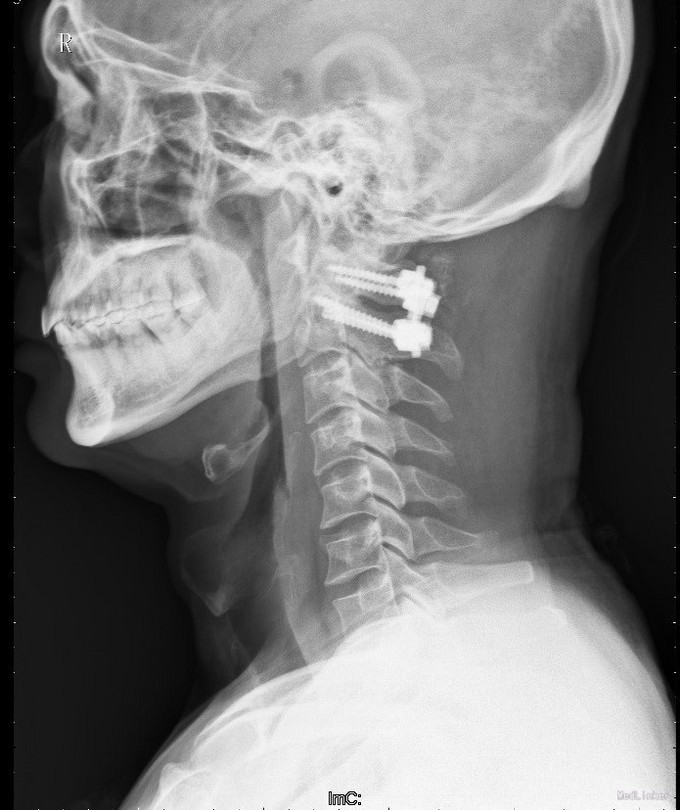

诊断:1.陈旧性寰枢关节旋转脱位2.陈旧性寰椎前弓骨折 治疗:全麻下行:行经前路寰枢椎脱位切开撬拨复位+经后路寰枢椎侧块螺钉内固定、去髂骨后外侧植骨融合术

手术顺利,术后病人返回SICU监护,病情平稳后转入我科,给予营养神经、祛痰、雾化吸入、补液等对症支持治疗,现患者恢复良好,颈部疼痛缓解,四肢活动良好